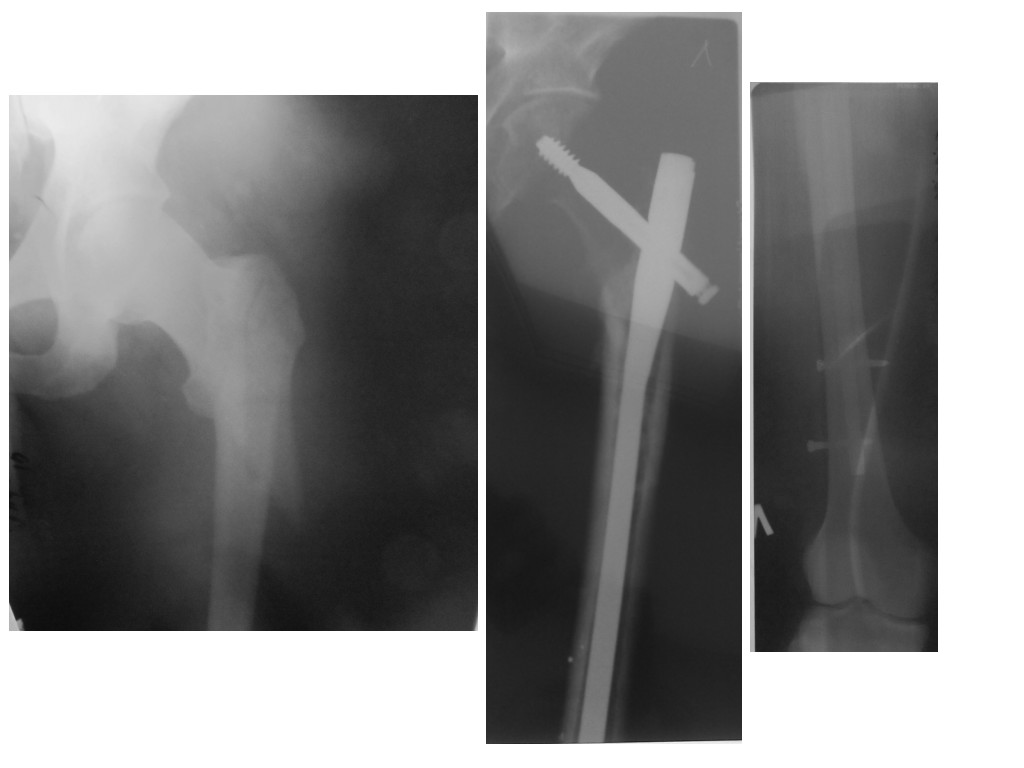

Здравствуйте, мне 30 лет, в сентябре 2015 года попал в ДТП. В местной больнице была проведена операция остеосинтез левой бедренной кости.

Операция прошла не совсем удачно - не смогли до конца закрутить один из нижних болтов, сорвали резьбу. Врач сказал через год всю конструкцию необходимо снимать. Беспокоят вопросы: можно ли удалить такую конструкцию и снова ходить на своих ногах? Будут ли чем-то заполнять отверстие от бедренного проксимального болта? Где лучше сделать такую операцию? Снимки прилагаю к сообщению.